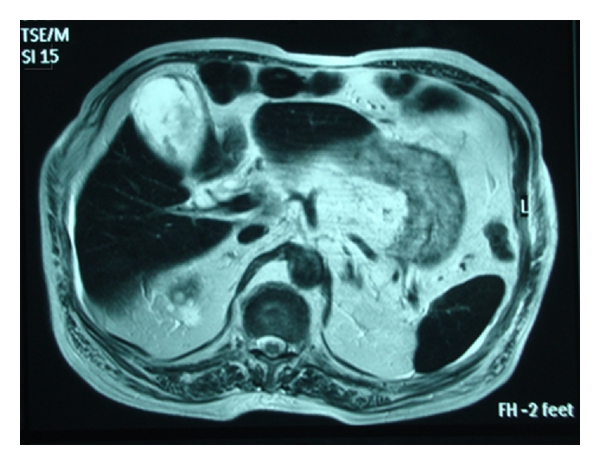

On the second day of hospitalization, the patient became febrile and developed right upper guardant guarding. Mild jaundice was also present. The patient remained hemodynamically stable. A complete blood count revealed white blood cell count (WBC) 16840/mm3, absolute neutrophils count 14730/mm3, and no differences in hemoglobin. Biochemical tests were remarkable for hyperbilirubinemia and elevation in transaminases, alkaline phosphatase (ALP), and gamma-glutamyl transpeptidase (GGT). A new ultrasound scan obtained and showed evidence of a distended thick-walled GB containing echogenic bile, pericholecystic fluid and a biliary tract with normal echoes and without dilation. Heavily T2-weighted MRI depicted a distended wide double borders (cholecystitis-like) GB enhanced by mixed signal intensity (hemorrhagic or exudative-like) component and intraluminal air (Figure 2). In MRCP, biliary tract appeared normal (Figure 3).